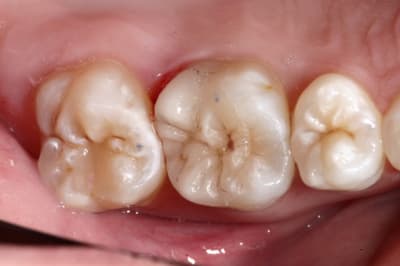

Pour abonder dans le sens qu'il ne faut pas couronner dans tous les cas, voici un cas fait il y a un an.

Les facteurs qui m'ont amené à prendre la décision de faire une endocouronne (proche d'un onlay en vérité) :

- 3 parois solides, la dernière pas trop fine.

- limites toutes supragingivales

- occlusion favorable (pas de photos de l'antagoniste je n'y ai pas pensé)

- patient réceptif

- grande profondeur de la chambre pulpaire (pas très visible sur les photos verticales)

Je n'en fais pas souvent mais quand j'en fait c’est que j'ai confiance. Faire une couronne classique ? Sur ce cas rien que de préparer les limites périphériques et on se retrouve avec une dent à raz la gencive, avec obligation de faire un (ou plusieurs) tenons longs pour une bonne rétention, générateur de fracture radiculaire....

Couronne Emax, collée au Multilink Automix

PS : avant toute remarque, non la patiente ne veut pas que je touche à sa dent de lait résiduelle ;o)